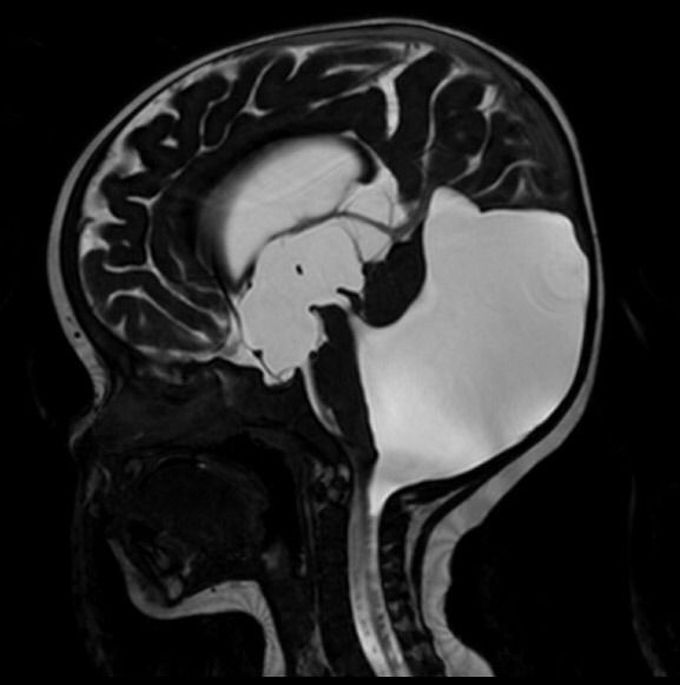

Dandy-Walker malformation (DWM) is the most common posterior fossa malformation, characterised by the triad of: 1. hypoplasia of the vermis and cephalad rotation of the vermian remnant 2. cystic dilatation of the fourth ventricle extending posteriorly 3. enlarged posterior fossa with torcula-lambdoid inversion (torcula lying above the level of the lambdoid due to abnormally high tentorium)